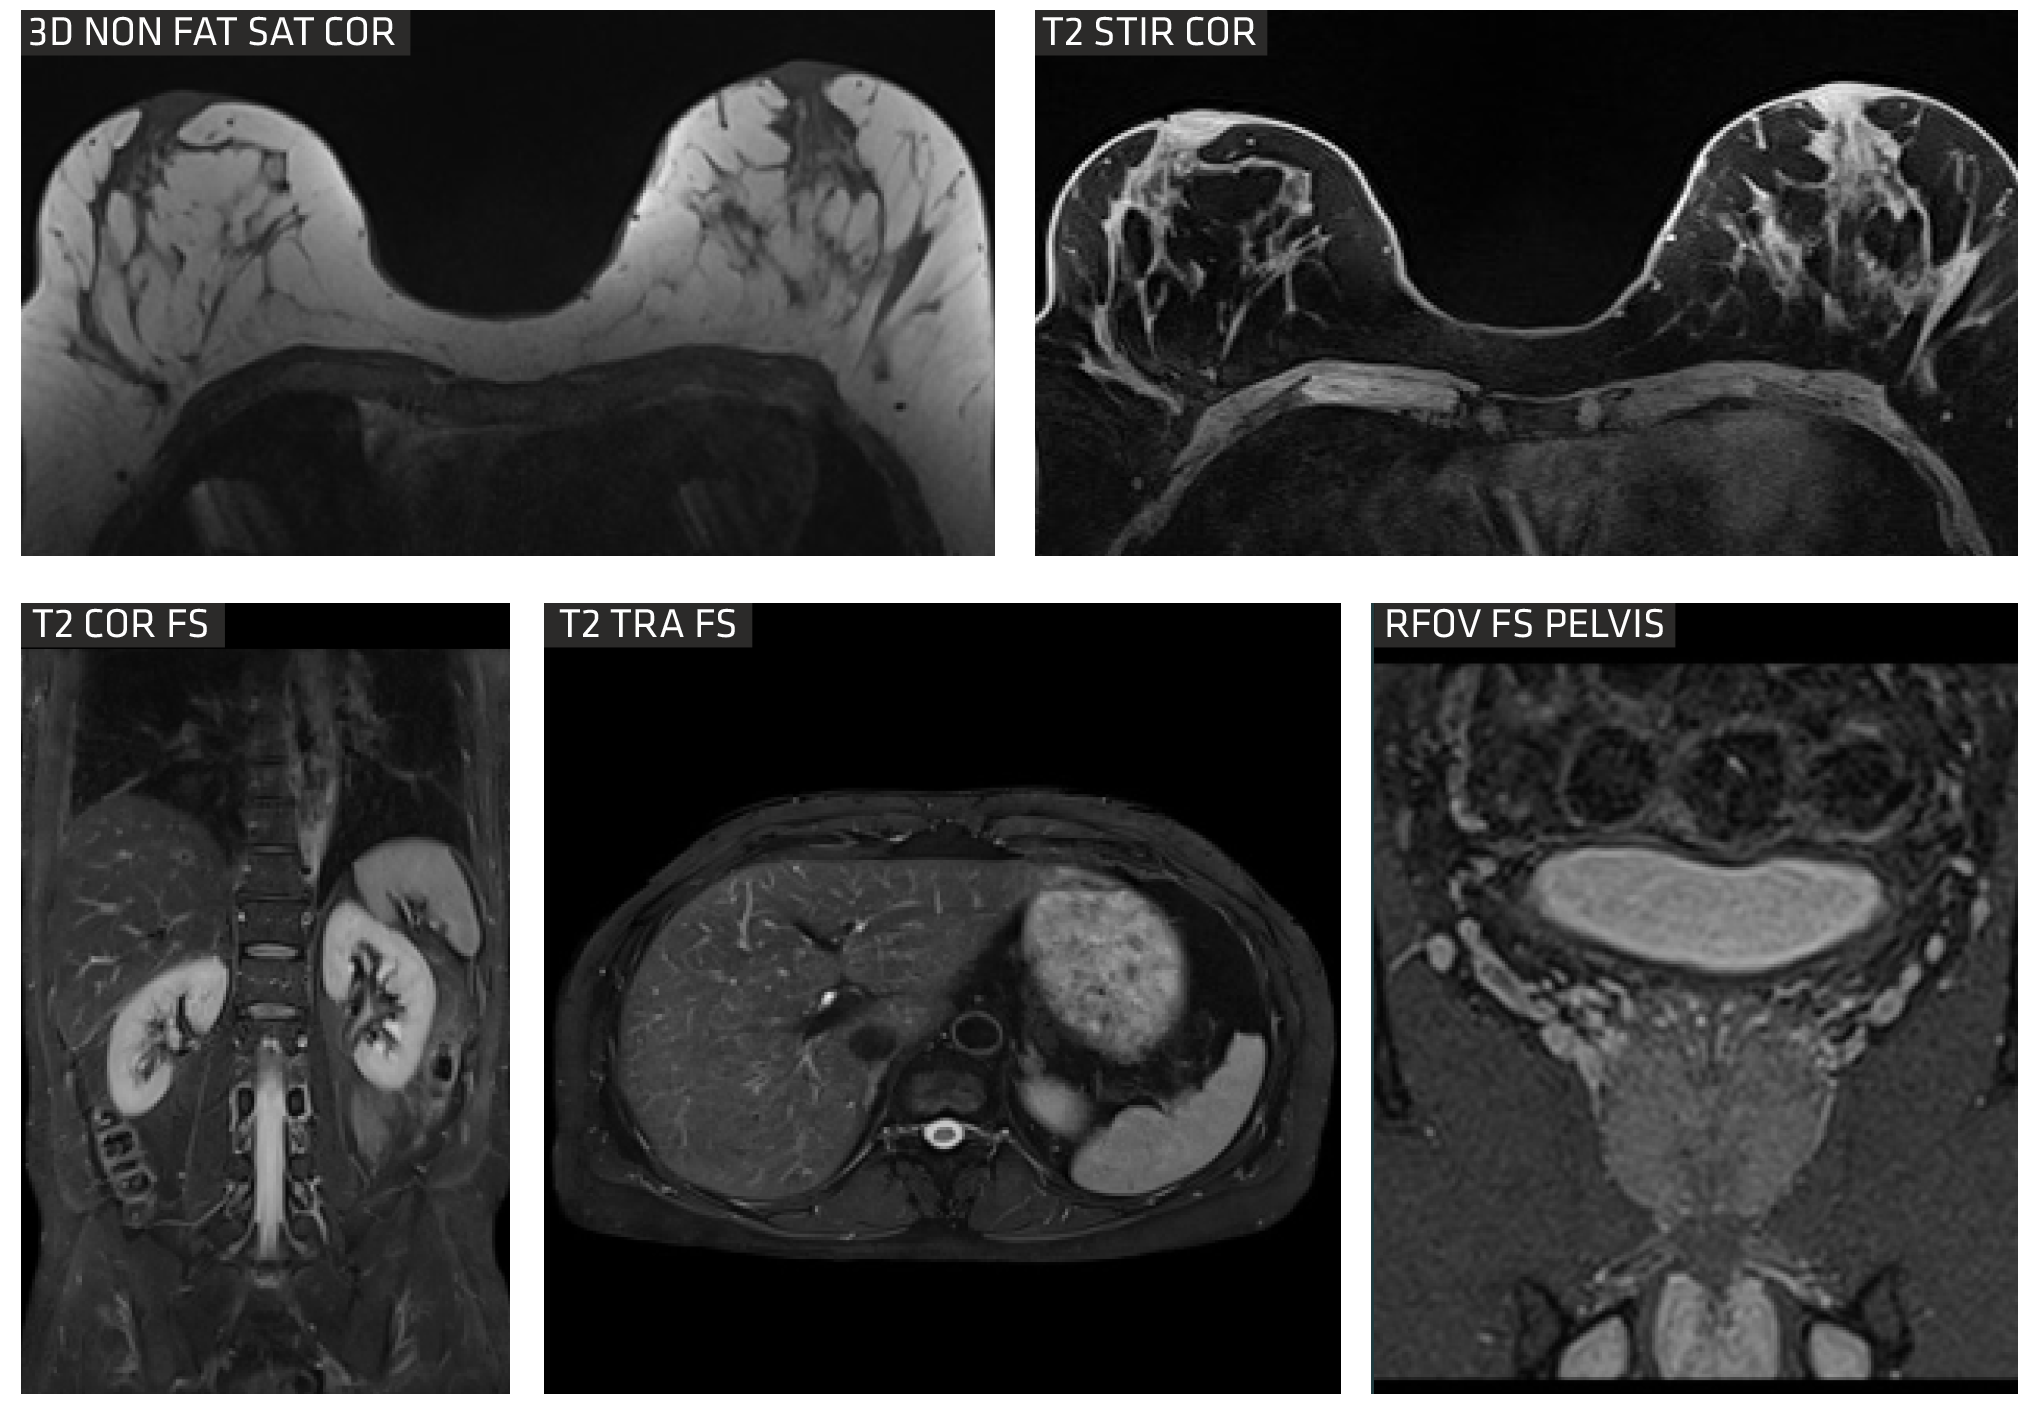

DIXON is a relatively new gradient-echo MR sequence that helps us visualize fat and water content in anatomical structures. It is reported to be useful in abdominal and brain imaging.

Non-contrast-enhanced (NCE) renal magnetic resonance angiography (MRA) serves as an excellent alternative to the conventional contrast-enhanced approach. This method eliminates the need for ionizing radiation and avoids the injection of gadolinium, a contrast material. The advantages include minimized patient discomfort, reduced examination expenses, and the avoidance of potential risks associated with nephrogenic systemic fibrosis.

rFOV

DWI can be applied on spine, uterus and pros tate, and increases clinical confidence in the diagnosis of numerous common pathologies.

Advanced Body imaging

The Sequoia Healthcare Clarity 1.5T oers comprehensive body imaging solutions with advanced tools tailored for patients. Its Free Breathing (ARCUS) MR Imaging protocols primarily utilize either breath-holding techniques or respiratory gating to eectively minimize motion-related artifacts, ensuring clearer and more accurate imaging results.